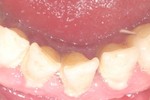

Czy to prawda, że raz do roku można bezpłatnie usunąć kamień? Jeśli tak, to czy ze wszystkich zębów? Odpowiedzi na te pytania udziela lek. stom. Wioletta Bereziewicz.